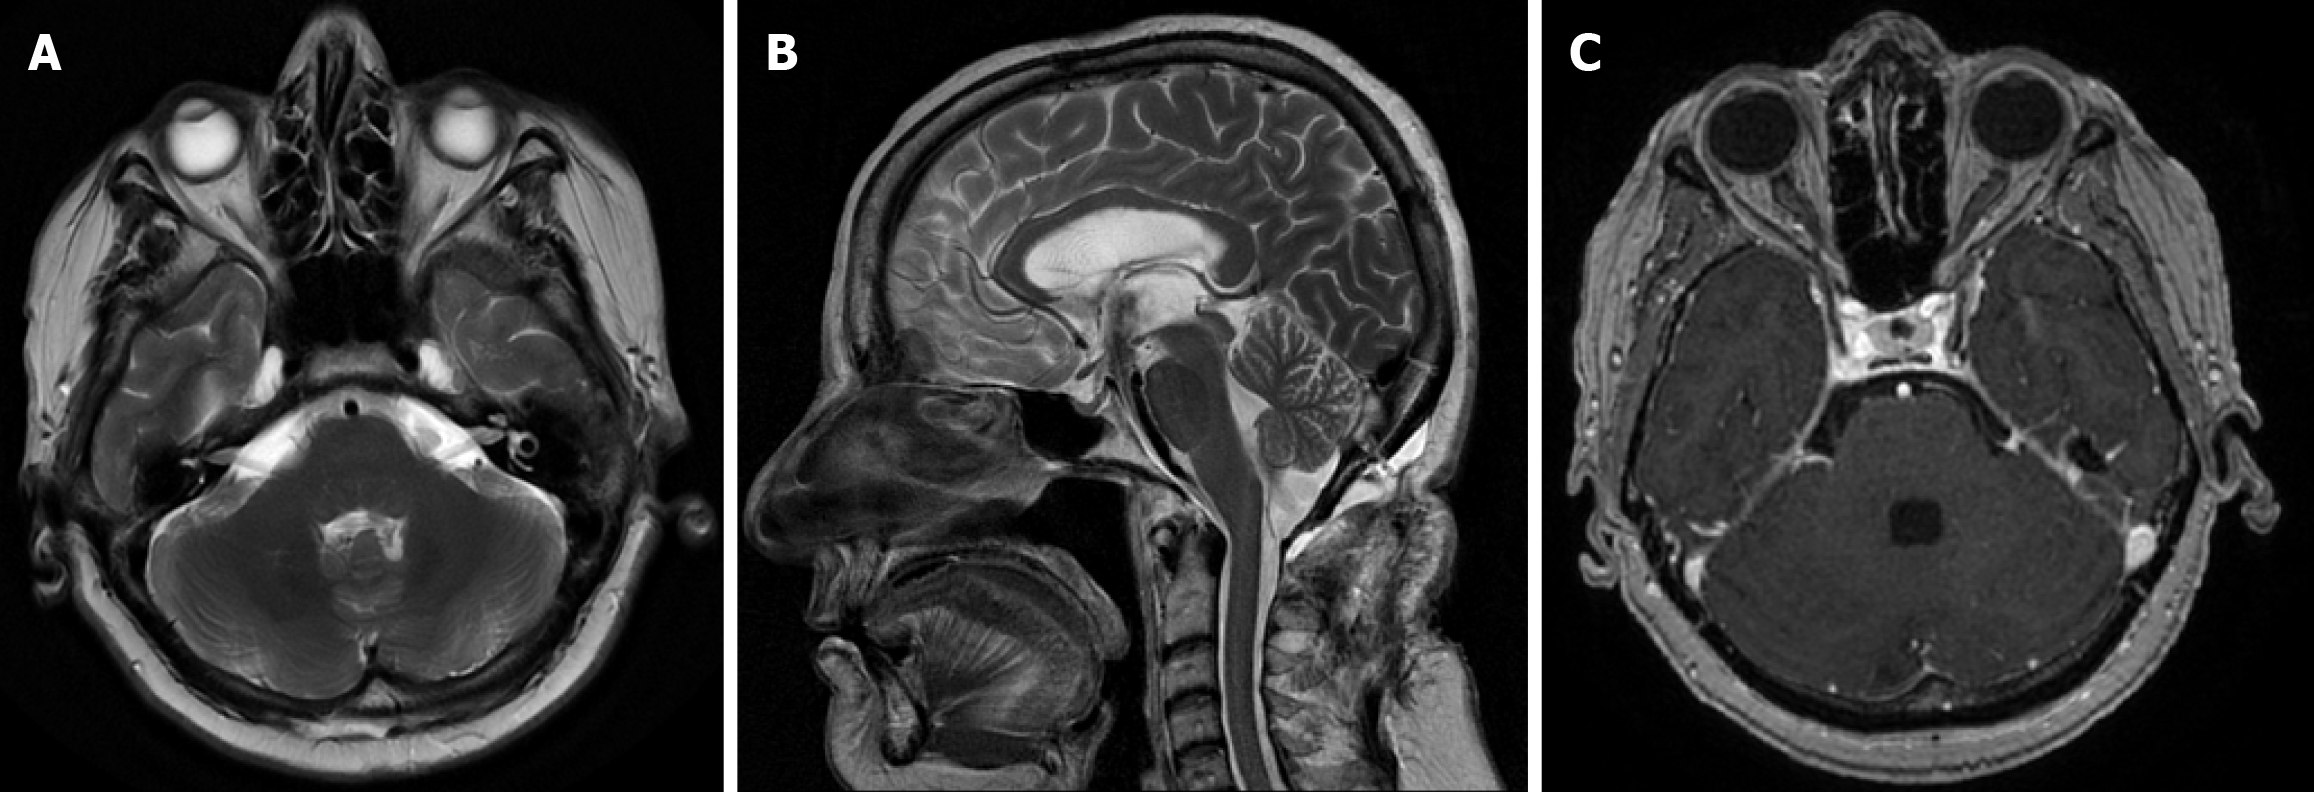

Magnetic resonance imaging (MRI) of the brain with gadolinium revealed a well-defined fourth ventricular cystic lesion, leading to tri-ventricular hydrocephalus (Figure 1). A small blurred-enhancing nodular component (5 mm) was observed within the cyst, adjacent to the right margin of the thickened cystic wall. A cerebral catheter angiogram was then performed to rule out a posterior fossa hemangioblastoma, initially considered in the differential diagnosis.

The MRI scans were carefully reviewed, and the radiological features—particularly the eccentrically located scolex within a thin-walled cyst—were highly suggestive of NCC in the vesicular stage.

However, 5 weeks later, the patient was readmitted with recurrent headaches, vomiting, and gait ataxia. A repeat brain MRI demonstrated a significant increase in the size of the fourth ventricular cystic lesion (Figure 1).